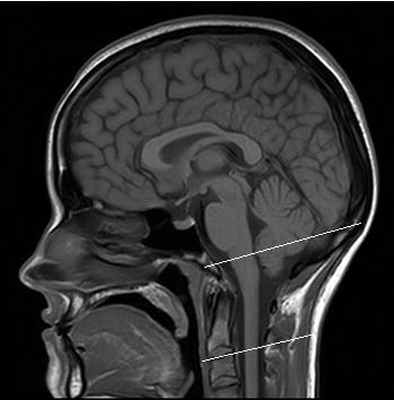

МРТ краниовертебрального сочленения в сагиттальной плоскости (А) и художественное исполнение (Б).

Показаны покровная мембрана (стрелка) и поперечная связка атланта (толстая стрелка).

БА — базион; ОП — опистион; ПМем — передняя атланто-затылочная мембрана; ЗМем — задняя атланто-затылочная мембрана;

З—Зуб; Ост2 — остистый отросток С2;ПД — передняя дуга атланта (тонкая стрелка); ЗД — задняя дуга атланта. Крестообразная, поперечная, крыловидные и добавочные связки.

А. МРТ во фронтальной плоскости. Б. рисунок.

МРТ головного мозга — белыми линиями отмечен краниовертебральный переход